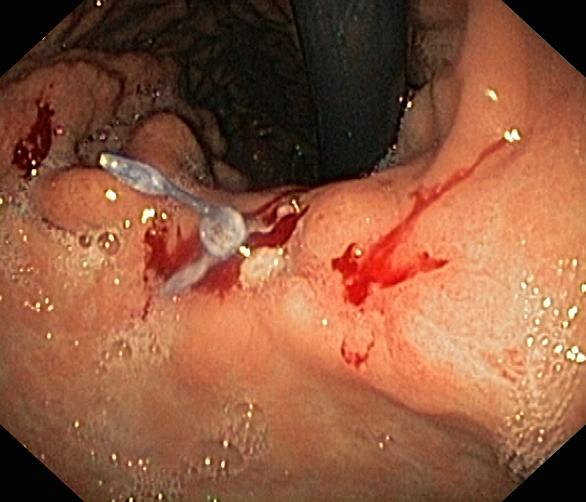

Krwawienie